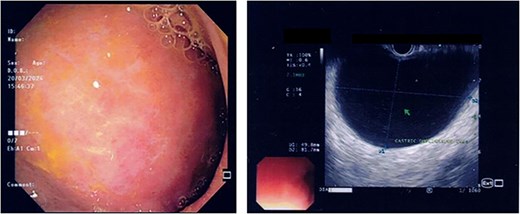

US HBS revealed a cystic lesion in the right liver lobe, raising suspicion for malignancy. OGDS showed a large non-communicating mass, within the distal wall of the greater curvature (Fig. 1). Endoscopic ultrasound (EUS) revealed a well-circumscribed, homogenous stomach cyst (79 × 100 mm). A CT workup was conducted for further clarification, reaffirming the presence of a distinct cystic lesion in the stomach and liver, without signs of malignancy (Fig. 2). At this stage, our findings suggest a large GDC and a coexisting benign hepatic cyst.

Endoscopic images demonstrate a subepithelial mass externally compressing the antrum. Endosonography revealed a well-defined, homogenous lesion with delineation across multiple gastric wall layers.